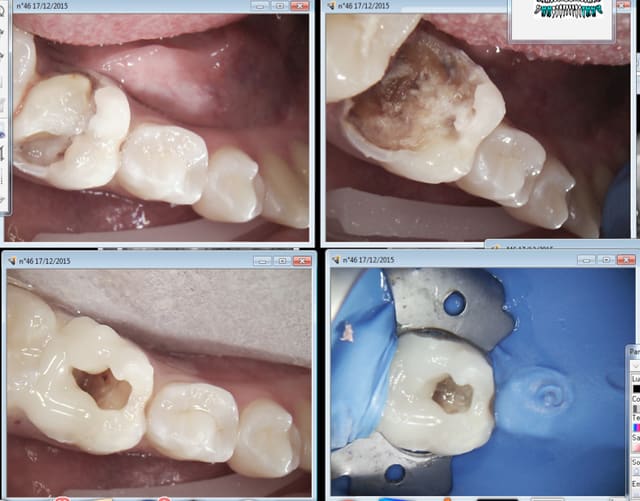

17/12/2015 à 12h10

Bon là ca s'est barré à la fin. -)))))

Endo moyenne.

Capture d e cran 2015 12 17 11.04 - Eugenol

Capture d e cran 2015 12 17 11.07 - Eugenol